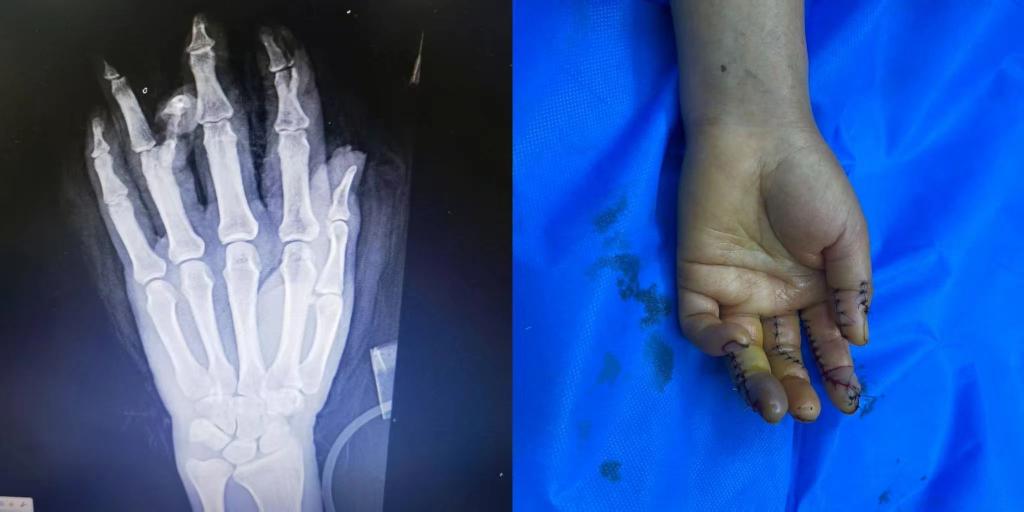

5月1日下午15点30分,Beat365中国唯一官方网站第五临床医学院2020级临床医学班的学生小马(化名)接到了来自伊犁亲戚的电话。电话中得知,亲戚在工作中不幸遭遇意外,左手被机器压伤,导致拇指、食指、中指、无名指均受到不同程度的损伤,受伤最严重的是食指和无名指,竖向劈开了骨头。由于多指多段离断的严重毁损伤,手术难度很大,当地医院的条件有限,为保住患者手指,需要申请前往上级医疗机构治疗。

随后,患者被送入手术室,由李华医生主刀,进行了长达7个小时的断指再植手术。

术后患者损伤严重的手恢复了基本形态,手指末梢血液循环逐步恢复。目前患者的情况基本平稳,在医院等待进一步观察和恢复。